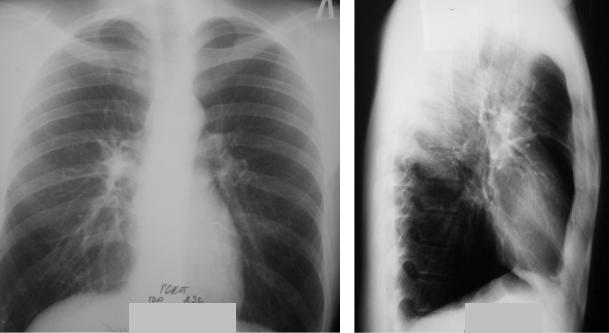

Симптомы и лечение инфильтративного туберкулеза легких

Раздел: Снимки-откровения